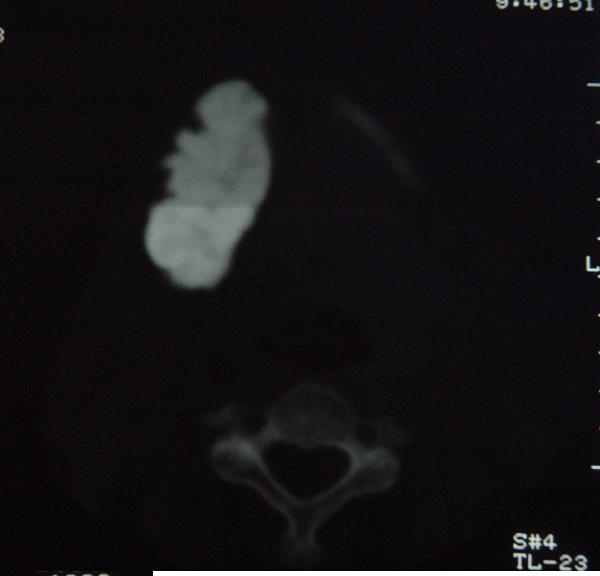

标题: CT12465:下颌骨肿瘤,请会诊 [打印本页]

标题: CT12465:下颌骨肿瘤,请会诊

发现下颌骨肿瘤近30年.逐渐增大.

考虑右侧下颌骨水平部及升部骨纤维异常增殖症可能性大。